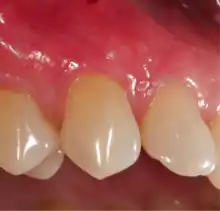

Post-gingival graft

Following this procedure, patients have an improved quality of recovery and require less recovery time due to enhanced healing factors.[16][17][18][19]